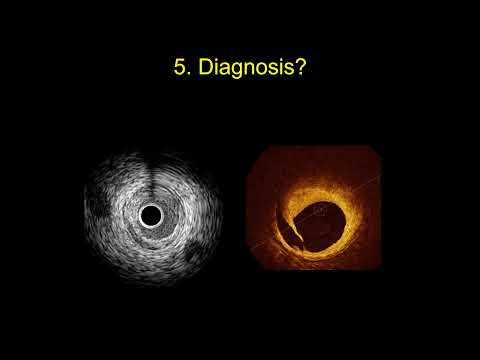

Essentials of IVUS and OCT

Intravascular imaging for guiding revascularization: when to use IVUS and when to use OCT?

IVUS OCT Optimizing Complex PCI, A MUST! - Farouc A Jaffer, MD